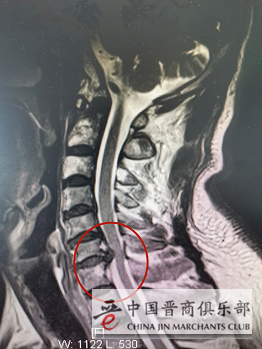

患者术前影像

经我院脊柱科医生详细询问病史、体格检查,结合颈椎磁共振检查提示:颈椎间盘突出,对应节段脊髓受压明显。脊柱科主任韦向荣指着受压脊髓说:“这就是引起胳膊和手麻木的原因,目前病情呈进行性加重,保守治疗已毫无意义,必须及时手术,解除脊髓神经压迫。”经韦向荣主任团队医生术前充分准备,完善术前常规,排除手术禁忌症,给蔺先生采用了“零切迹”椎间融合器材料实施了ACDF(颈椎前路椎间盘切除减压植骨融合术)手术。